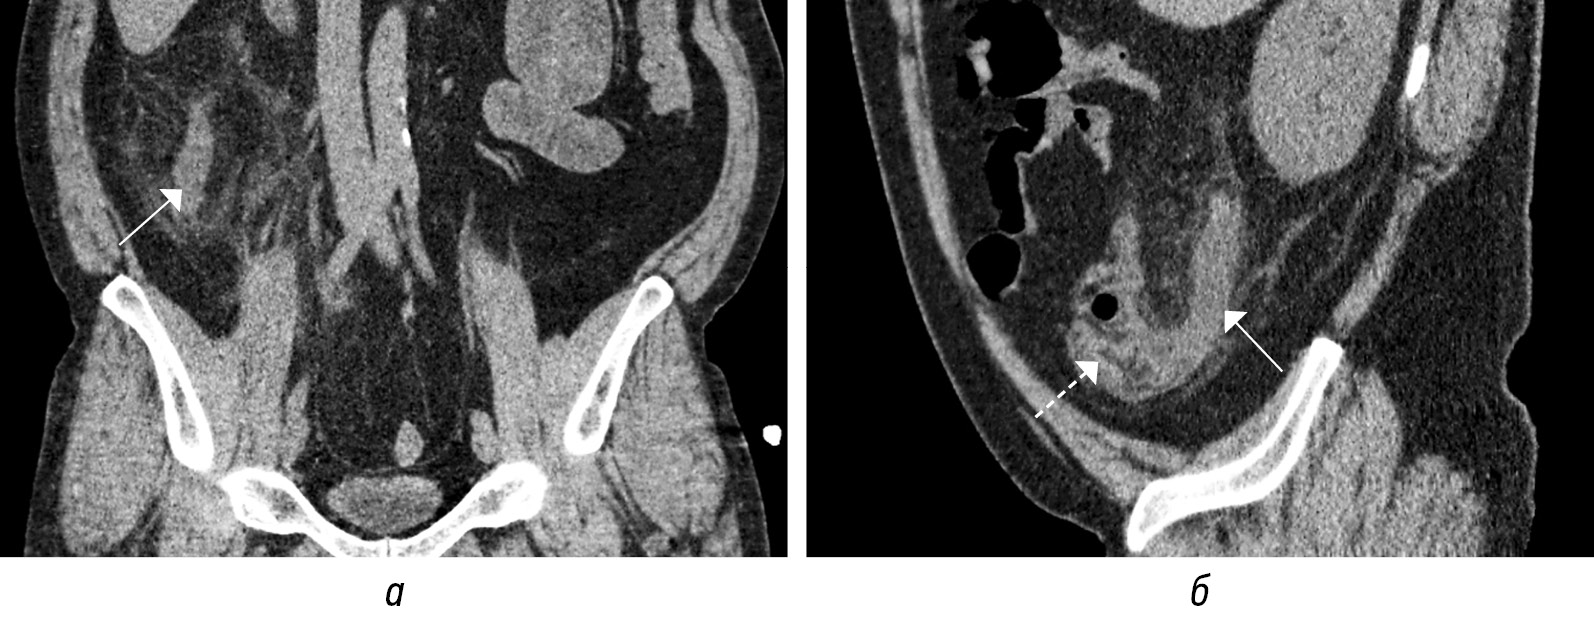

Осложненный ОА характеризуется либо перфорацией (тип 3), либо ожидаемой перфорацией (тип 2). Ключевым визуализационным признаком осложненного ОА являются выраженные изменения периаппендикулярной ткани: гиперэхогенность на УЗИ или тяжистое уплотнение на КТ. Выраженная, но все еще локализованная периаппендикулярная жидкость или обструкция наблюдается при тяжелом флегмонозном ОА (тип 2а). Гангренозный ОА (тип 2б) характеризуется наличием интрамурального газа и/или потерей эхогенного подслизистого слоя. Некоторые авторы классифицируют тяжелый флегмонозный ОА (тип 2а) и даже гангренозный ОА (тип 2б) как неосложненный ОА, предположительно потому, что они определяют осложнения исключительно по наличию перфорации. Нoffmann J.C. et al. предлагают классифицировать эти типы как осложненные ОА в соответствии с консенсусным заявлением Европейской ассоциации эндоскопической хирургии, опираясь на многочисленные исследования, показавших, что аппендиколит с обструкцией (рис. 15, а–г), выраженное периаппендикулярное воспаление и гангрена указывают на неизбежную перфорацию [2]. Перфорация может быть прикрытой с абсцессом (тип 3а) или неприкрытой со свободной жидкостью, газом и гноем в брюшной полости (тип 3б). Иногда можно обнаружить псевдообразование аппендикса за счет вовлечения в воспалительный процесс прилежащих петлей тонкой или толстой кишки, что также представляет собой локализованную форму перфорации, т. е. тип 3а.

Рис. 15. КТ-томограммы (а) в трех плоскостях на уровне аппендикса с наличием в нижней трети аппендиколита (на изображениях соответствует точке пересечения секущих линий) с обструкцией просвета и расширением просвета выше препятствия, с отеком периаппендикулярной жировой клетчатки. Сонограммы (б–г) в В-режиме демонстрируют аппендиколит, участки аппендикса без расширения просвета и мешковидное расширение выше препятствия (стрелка)

Fig. 15. CT-tomograms (a) in three planes at the level of the appendix with the presence of appendicolitis in the lower third (in the images corresponds to the intersection point of the secant lines) with obstruction of the lumen and expansion of the lumen above the obstacle, with swelling of the periappendicular fatty tissue. Sonograms (б–г) in B-mode demonstrate appendicolitis and areas of the appendix without expansion of the lumen and sac-like expansion above the obstacle (arrow)